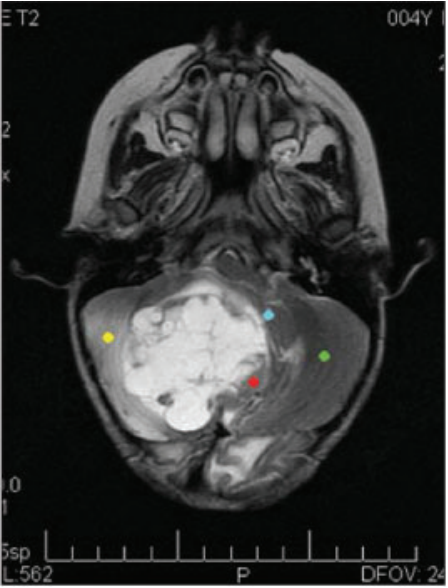

Para investigação de tumores da fossa posterior, foi obtida a seguinte imagem:

A referida imagem corresponde a:

Ressonância magnética, possibilitando avaliar tons de cinza na imagem, e, portanto, diferentes texturas que auxiliam reconhecer aspectos distintos dos tecidos.